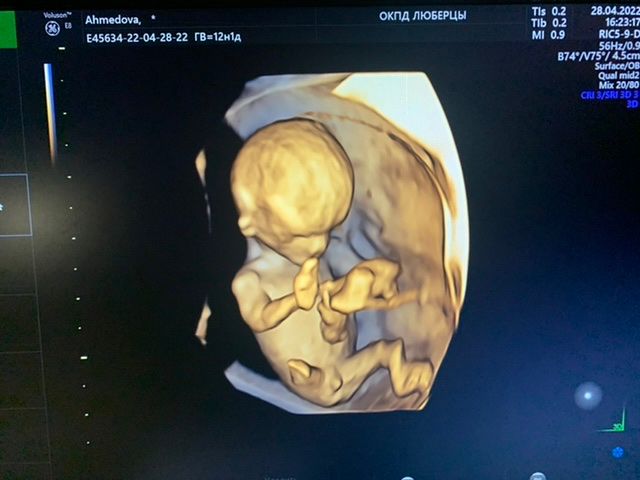

Здравствуйте подскажите какой пол у ребёнка? 12 недель

На таком сроке так пол не смотрят, не информативно ещё. А так чисто интуитивно по форме головы - мальчик)

Рано ещё судить) это может быть и клитор и половой член, но я за мальчика))(

Нужно смотреть в профиль, тут это будет пальцем в небо

Кажется что бугорок смотрит вверх, наверное мальчишка😊

Пока ещё ни кто точно не скажет ) половые органы не сформированы , но по фото сбоку я склоняюсь к девочке

На мальчика похож))

Не в этой проекции смотрят на ваших неделях) фото сбоку нужно )

Божечки, какой человечек в 12 недель) мне кажется девочка. Это вроде как нога в сгибе, а не писюшка.

Как думаете кто? Метод Рамзи